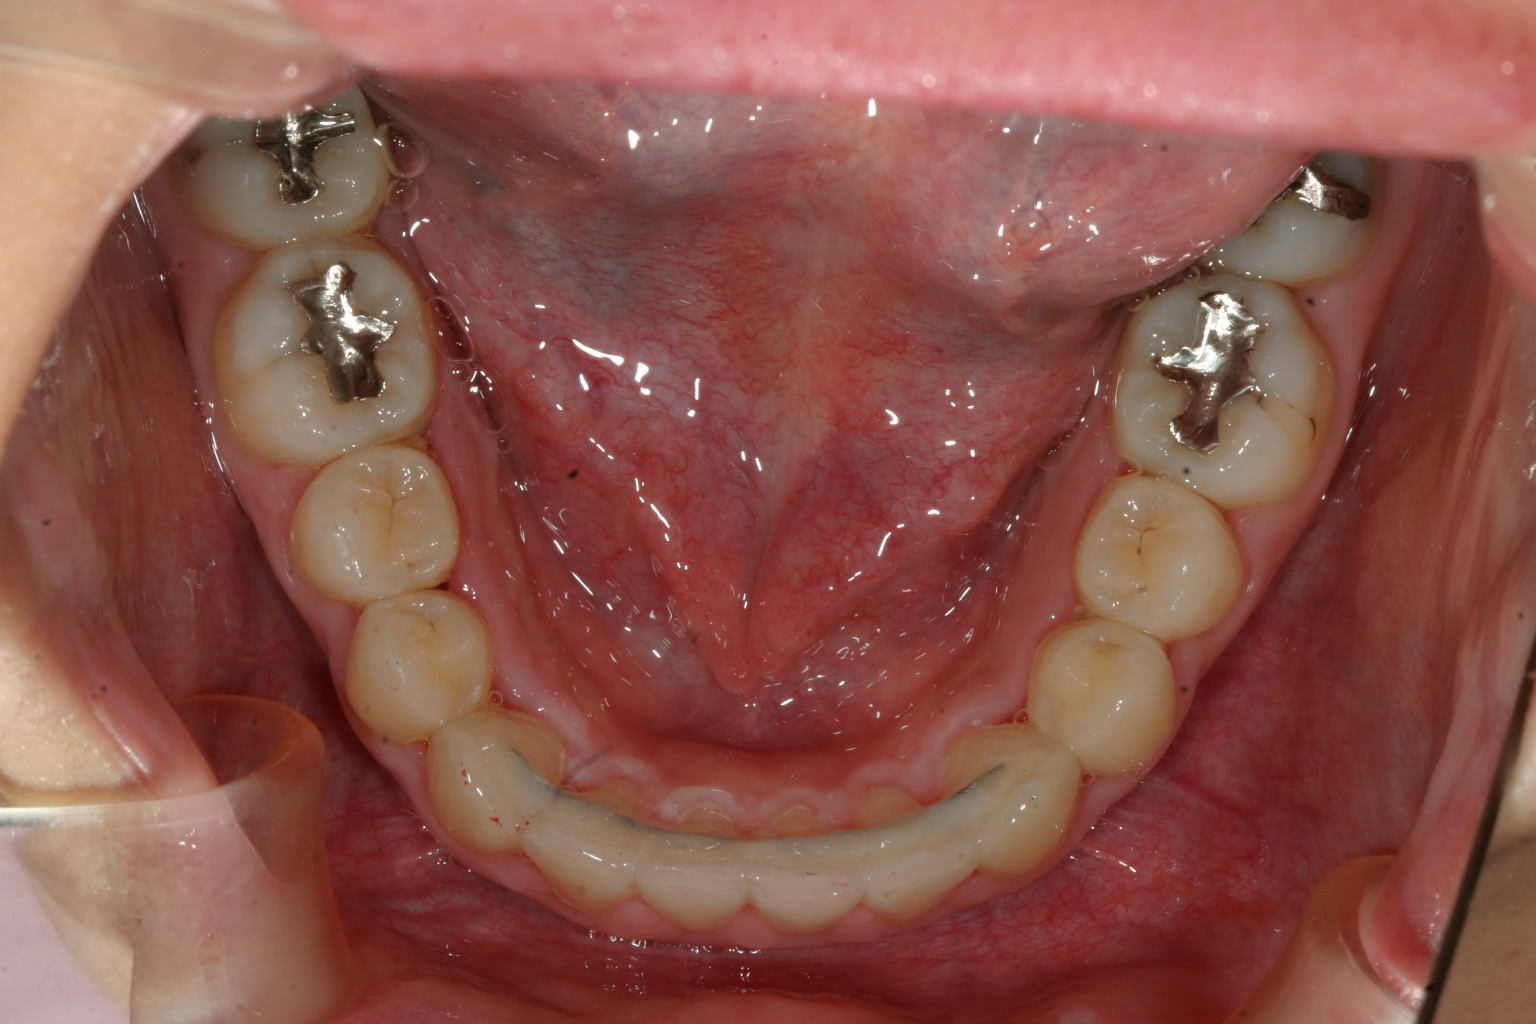

下顎はさほど問題無いですね~

下顎も少し犬歯間を広げてます。